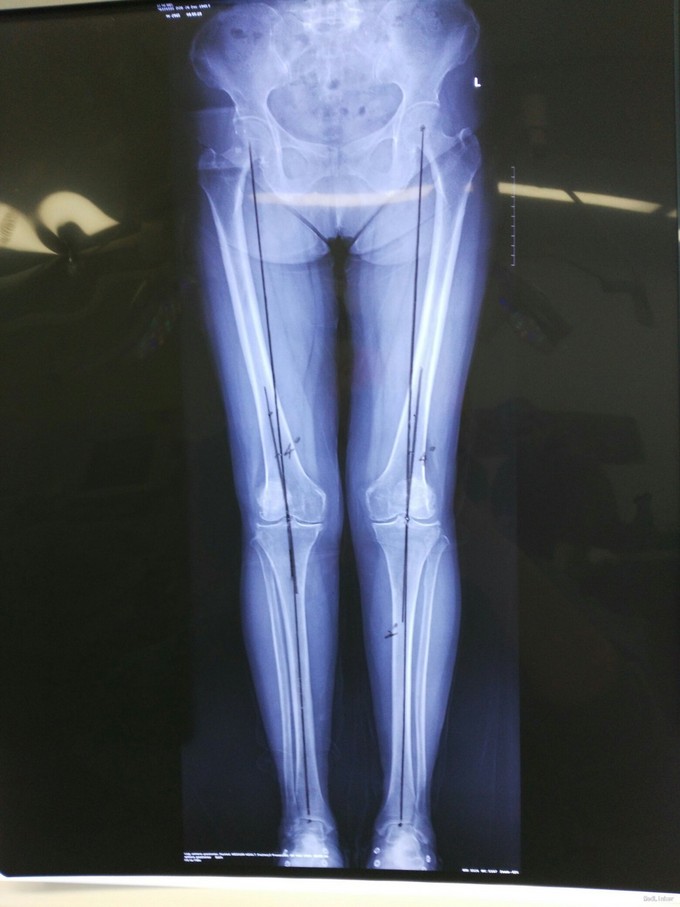

患者老年女性,68岁 主诉:双膝关节疼痛30年,加重2年 现病史:患者30年前无明显诱因间断出现双膝关节疼痛,为针扎样痛,无明显放射,休息、制动后可缓解,天气寒冷时疼痛有所加重,不伴弹响、僵直,不伴发热、盗汗。未规律诊治。2年前双膝疼痛再次加重,保守治疗无效。 既往史:诊断高血压病5年,最高150/90mmHg,规律服药,血压控制可。

查体:步入病房,步态基本正常,双侧膝关节外翻畸形,无屈曲畸形,四肢肌容量肌张力正常。 辅助检查:见图

诊断:双膝严重骨关节炎 治疗:双侧人工膝关节置换术